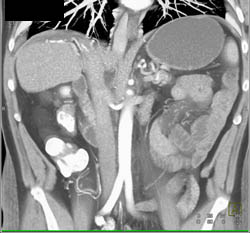

Subtle Tumor of Body of the Pancreas Encases the SMA and Aorta